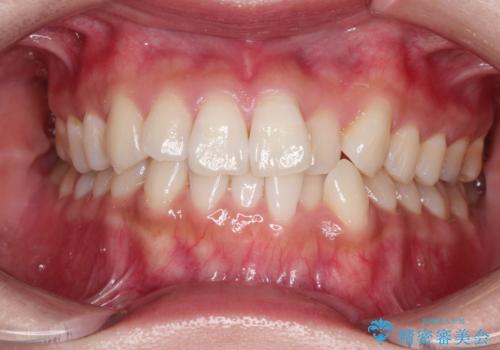

インビザラインでの前歯のガタガタの矯正

- 上下の前歯のがたつきを主訴に来院されました。

歯と歯の間をわずかに削りスペースを作り、インビザラインにて矯正治療を行うこととしました。

使用時間を守っていただけたので、スムーズに矯正を終了することができました。